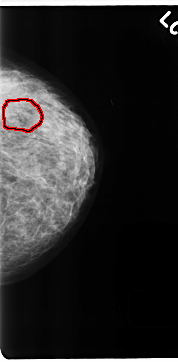

C_0199_1.LEFT_MLO

FILE: C_0199_1.LEFT_MLO.OVERLAY

TOTAL_ABNORMALITIES 1

ABNORMALITY 1

LESION_TYPE CALCIFICATION TYPE PLEOMORPHIC DISTRIBUTION CLUSTERED

ASSESSMENT 5

SUBTLETY 4

PATHOLOGY MALIGNANT

TOTAL_OUTLINES 1

BOUNDARY